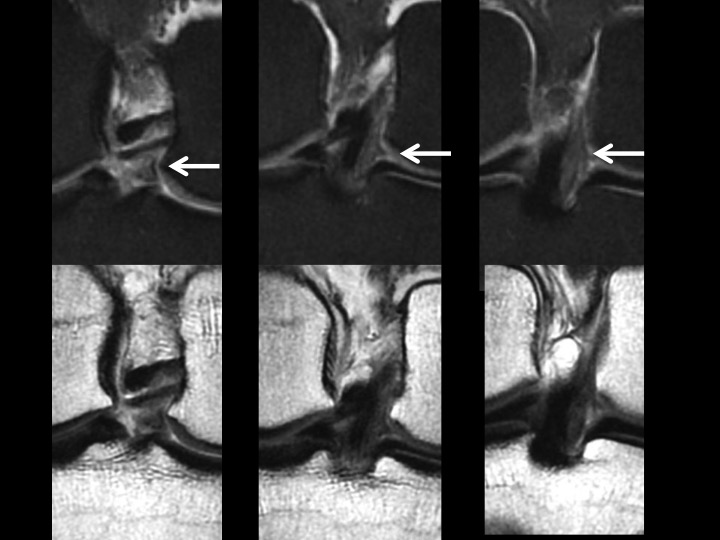

35M pain and swelling 1 month after fall playing basketball

There is intermediate signal soft tissue thickening along the medial aspect of the PCL with what appears to be a tear near the tibial insertion of the posteromedial bundle in the Sag images. The larger anterolateral bundle is intact, with minimal increased intrasubstance signal in the vertical segment. This is an isolated injury, so it will certainly be treated conservatively. I know there has been controversy over soft tissue thickening in this location, with reports of synovial thickening/scarring with intact PCL. Note that the opposite knee does not look like this (image 5). Even though this should heal with stability, I wonder if this might be the cause of scarring we sometimes see in this location and if it might not be a source of chronic pain and limitation. Thoughts? Reference article.

posteromedial bundle of posterior cruciate ligament ( RID2786 )